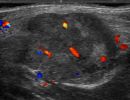

Πολλές αλλοιώσεις και παθήσεις μπορούν να απεικονιστούν υπερηχογραφικά και να μελετηθούν αξιόπιστα με τη βοήθεια του Έγχρωμου Doppler και της Ελαστογραφίας .

- Αιμαγγειώματα, αγγειοδυσπλασίες (αγγειακού τύπου βλάβες)